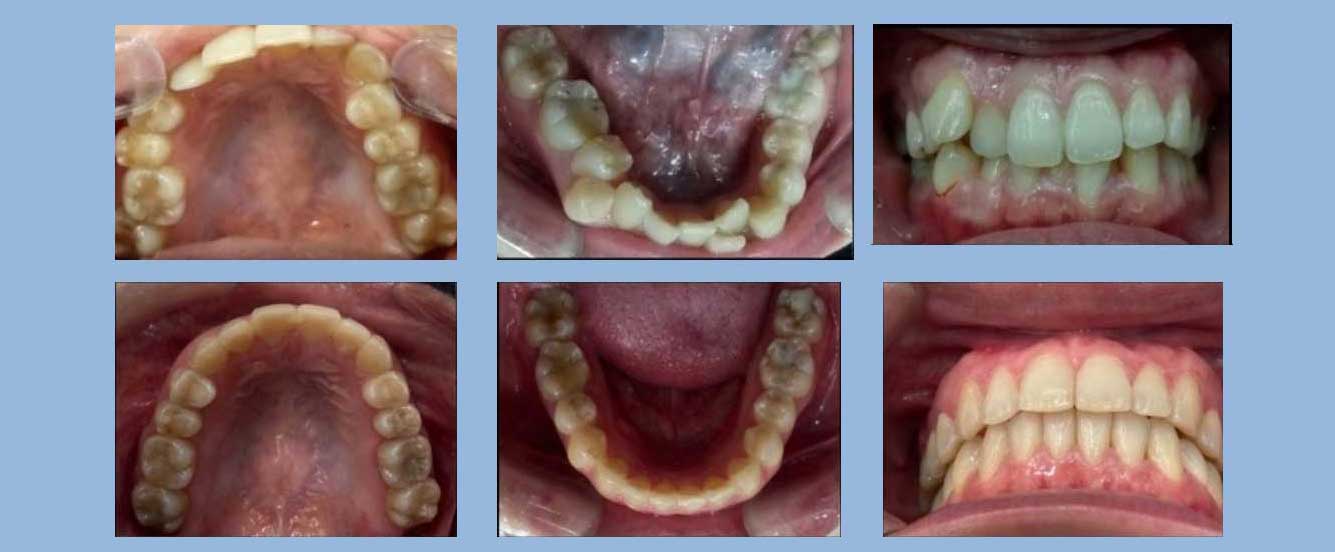

謝小姐 (56歲) 矯正完成

狀態 : 擠、暴牙、牙周病、矯正合併植牙